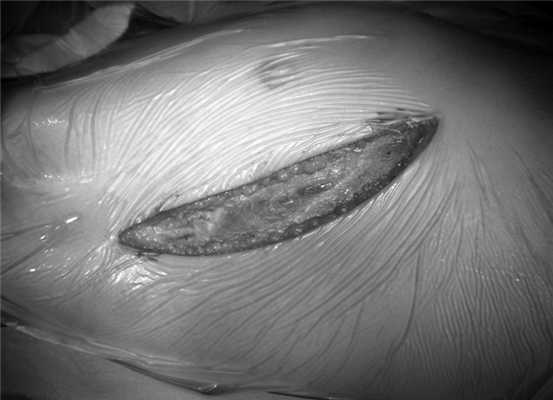

2) разрез кожи проводится от средней подмышечной линии книзу вертикально, по ходу края большой грудной мышцы и далее, обходя зону роста молочной железы (см. рисунок, б). Рисунок 1. Этапы операции при выполнении переднебоковой правосторонней торакотомии. б - кожный разрез. Частично кпереди пересекаются передние зубчатые мышцы. Широчайшая мышца спины не рассекается. Торакотомия выполняется по четвертому межреберью с рассечением максимально кзади;